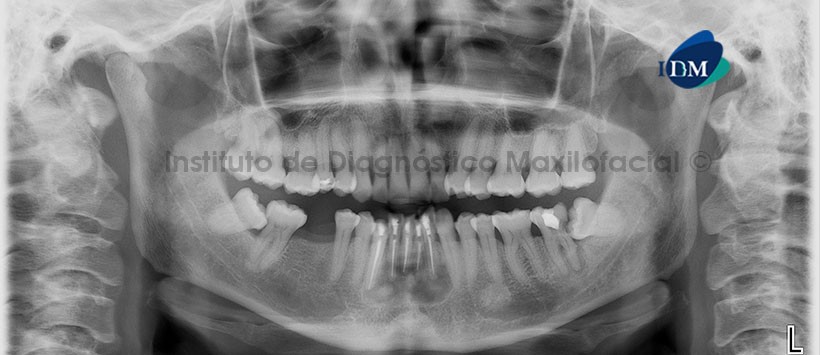

En la radiografía panorámica (Figura 1) se observa una imagen mixta de límites definidos bordes corticalizados en zona periapical de piezas 32, 31, 41, 42, 43; que a su vez presentan tratamientos de conductos radiculares. Además se observa una imagen radiolúcida a nivel periapical de la pieza 3.7 e imágenes radiopacas de densidad ósea a nivel periapical de las piezas 35 y 4.7.